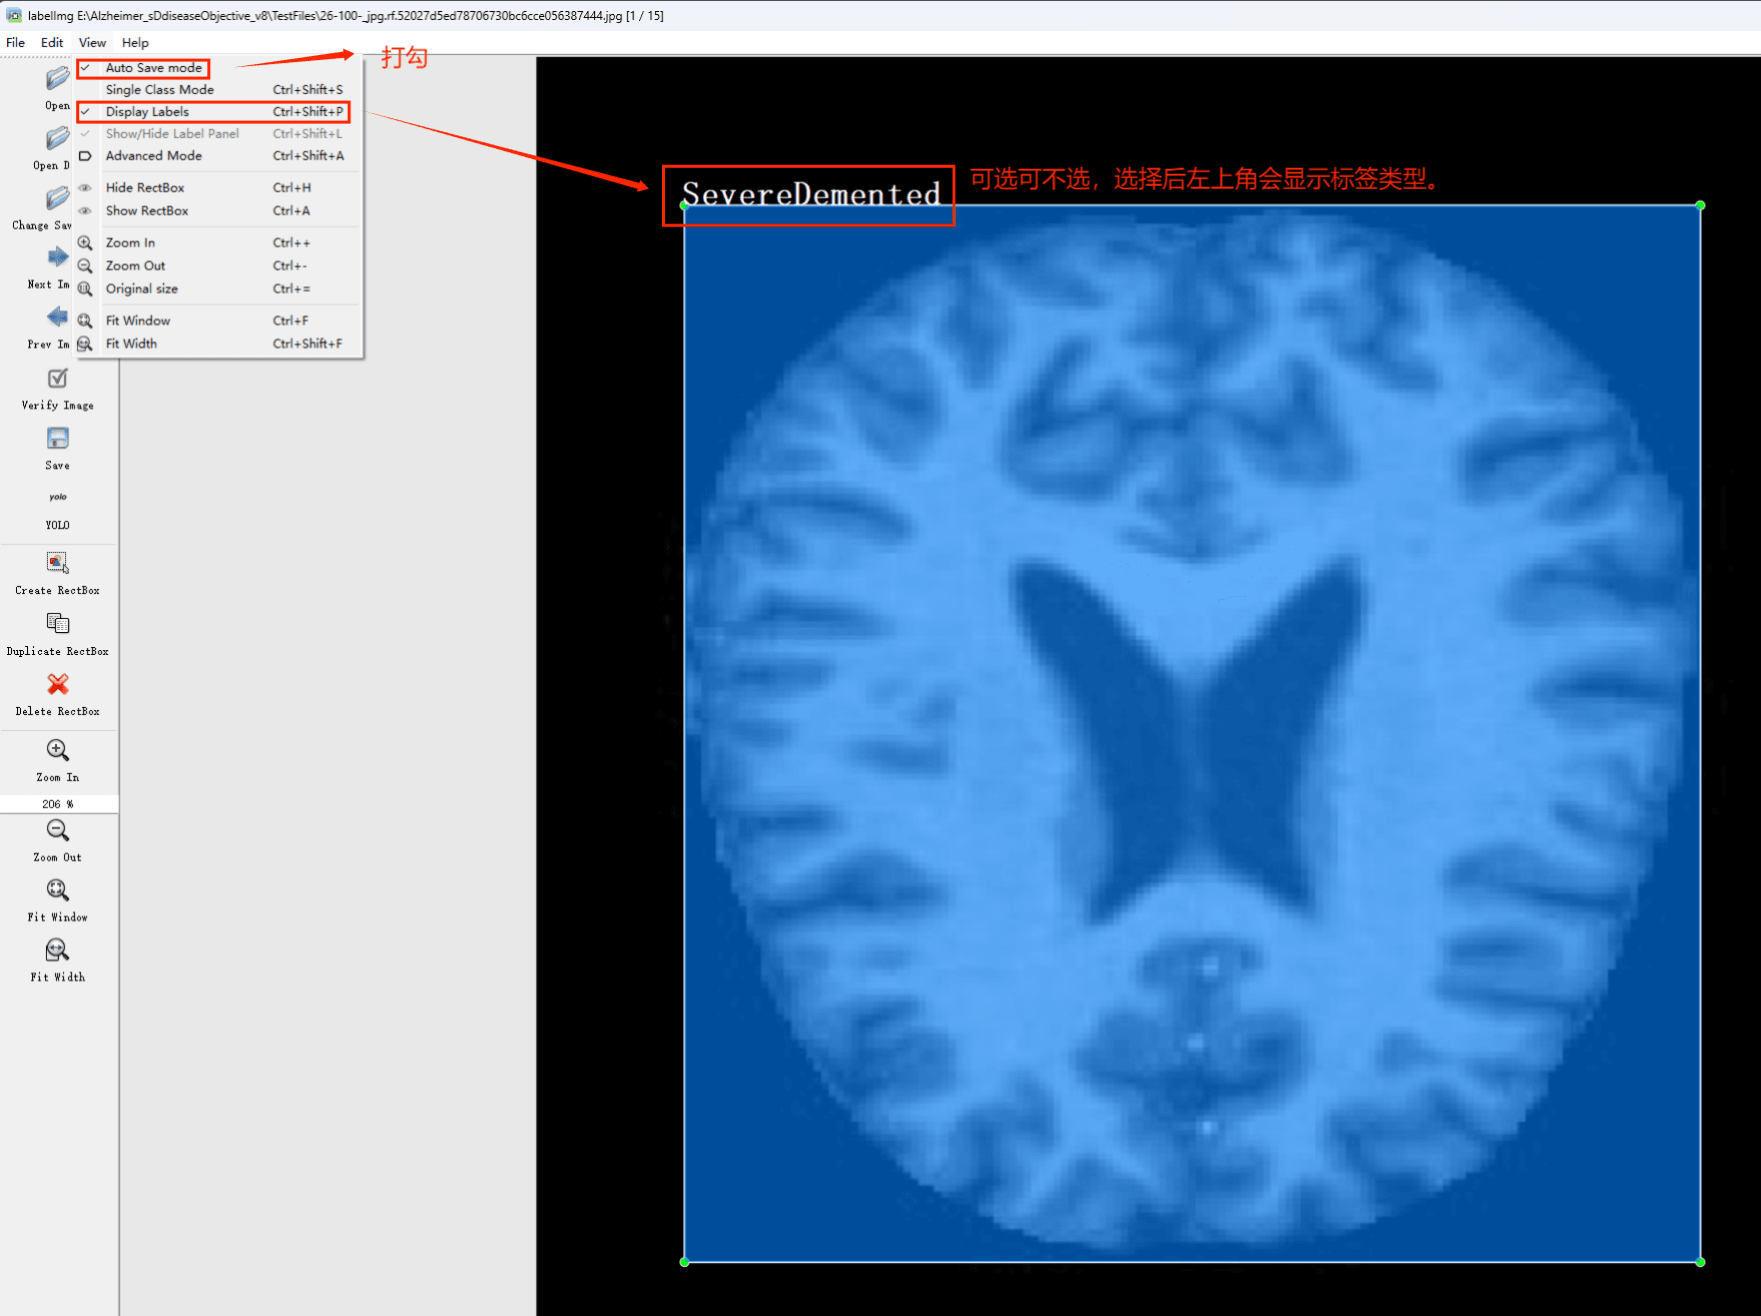

初识labelimg

打开后,我们自己设置一下

在View中勾选Auto Save mode

接下来我们打开需要标注的图片文件夹

并配置存储该图标的路径(如上所述)。开始执行标注流程:选择边界框工具,并为选定的目标添加标签。完成后,请切换至下一张图片继续标注。